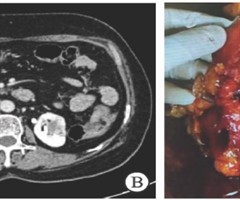

临床表现酷似肾盂癌的罕见良性肿瘤肾盂海绵状血管瘤1例报告及鉴另诊断思考

肾海绵状血管瘤临床较罕见,主要临床表现为间歇性血尿,部分表现为腰痛,易误诊为肾脏恶性肿瘤,导致手术方式选择不当,该病术前难以确诊,常通过术后病理确诊。贵州省人民医院(以下简称“我院")泌尿外科收治1例临床表现酷似肾盂癌的肾盂海绵状...